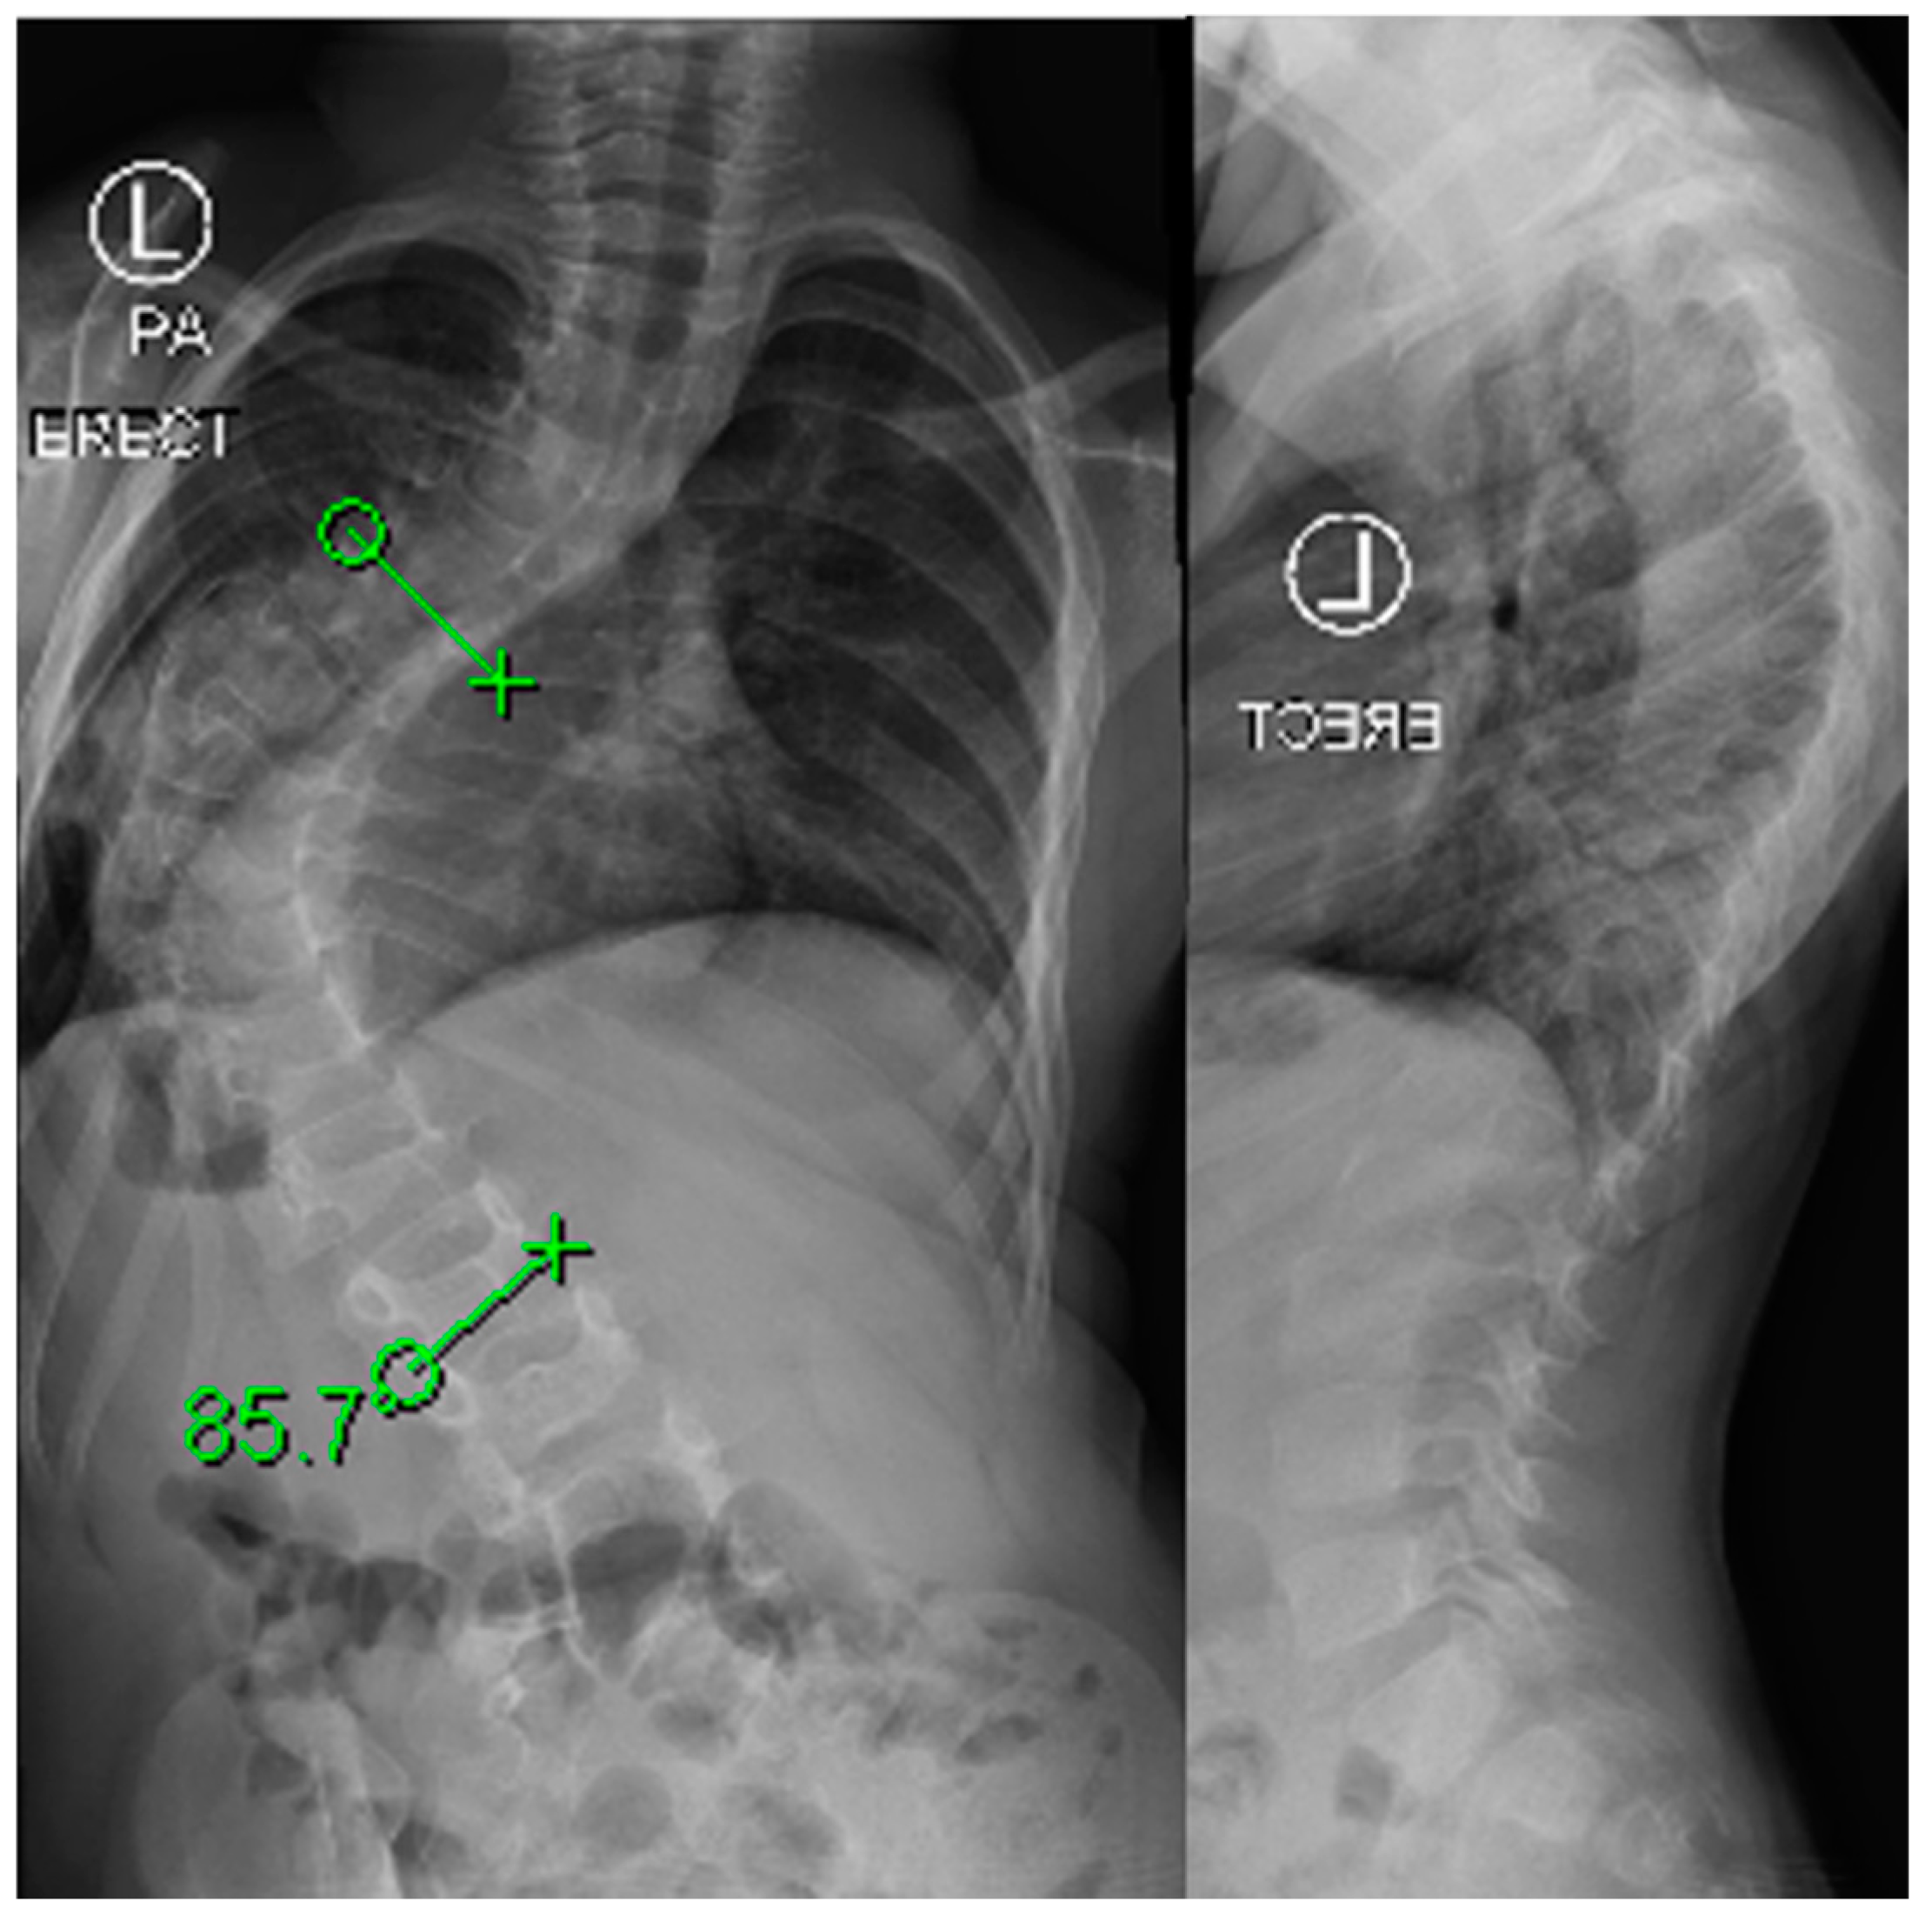

Initially developed for idiopathic scoliosis curves from 45–60 degrees, vertebral body tethering has recently been explored for older early onset patients [61,62,63]. In this population of 8–11 with Sanders scores less than four, dubbed “Tweeners”, VBT was shown to be as effective as MCGRs and PSF for correction of deformity. A clinical example is shown in Figure 6. In a study supplying direct comparison amongst the three, major scoliosis curve correction was seen in all three groups including by 41.1% with VBT, 52.2% with PSF, and by 27.4% with MCGRs. This same study demonstrated high rates of unplanned operations in MCGRs compared to PSF and VBT with 21.6% of MCGR, 16.2% of VBT, and 7.1% of PSF patients undergoing at least one unplanned revision. Technical considerations exist for VBT including instrumentation sizes that may not be appropriate for the smallest patients. Applying VBT to younger patients may not fully prevent the need for definitive fusion, however, it could prevent the progression of lumbar curves and make selective thoracic fusions more successful and limit lumbar instrumentation, although this is largely theoretical and should not diminish the morbidity of a secondary surgery. VBT does confer technique-specific complications including those associated with thorascopic and anterior surgery, overcorrection, and the risk of cord breakage which is seen in up to 50% of thoracic tethers and is as high as 70–80% in the lumbar spine [64]. While there are few studies examining the application of tethering in the early onset population, available data suggest it is an option in older early onset patients.

Figure 6. Pre- and postoperative imaging of a female patient with early onset scoliosis treated with anterior vertebral body tethering.